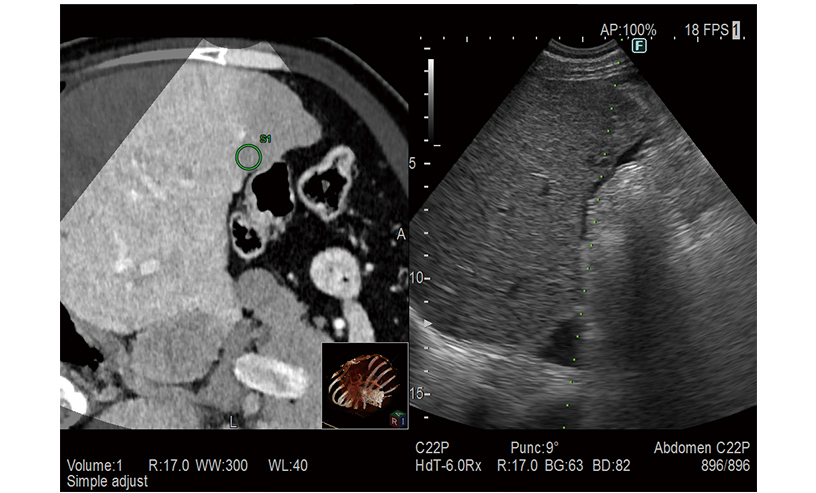

RVS is a function which fuses real-time ultrasound imaging with an MPR image created from the previously acquired CT, MRI or ultrasound volume data. RVS, a treatment supportting function by simultaneous display with other modalities, assists the positioning of treatment and the detection of small lesions that are difficult to find by ultrasound alone.

Provides simulation of single or multiple needle paths during navigation to a target with RVS. The positional relationship between the marked target and needle paths can be assessed in real time using the 3D body mark, reconstructed from the virtual CT volume data, with additional C-plane display orthogonal to the needle path.

A color map superimposed on the CT image simulates the distribution of the electric field (E-field) from the given location of multiple electrodes during RFA treatment. The simulation can be made with different positions of the multiple electrodes or additional ablation to determine the optimal arrangement. This flexibility in planning the needle path can bring improvement to the treatment technique.